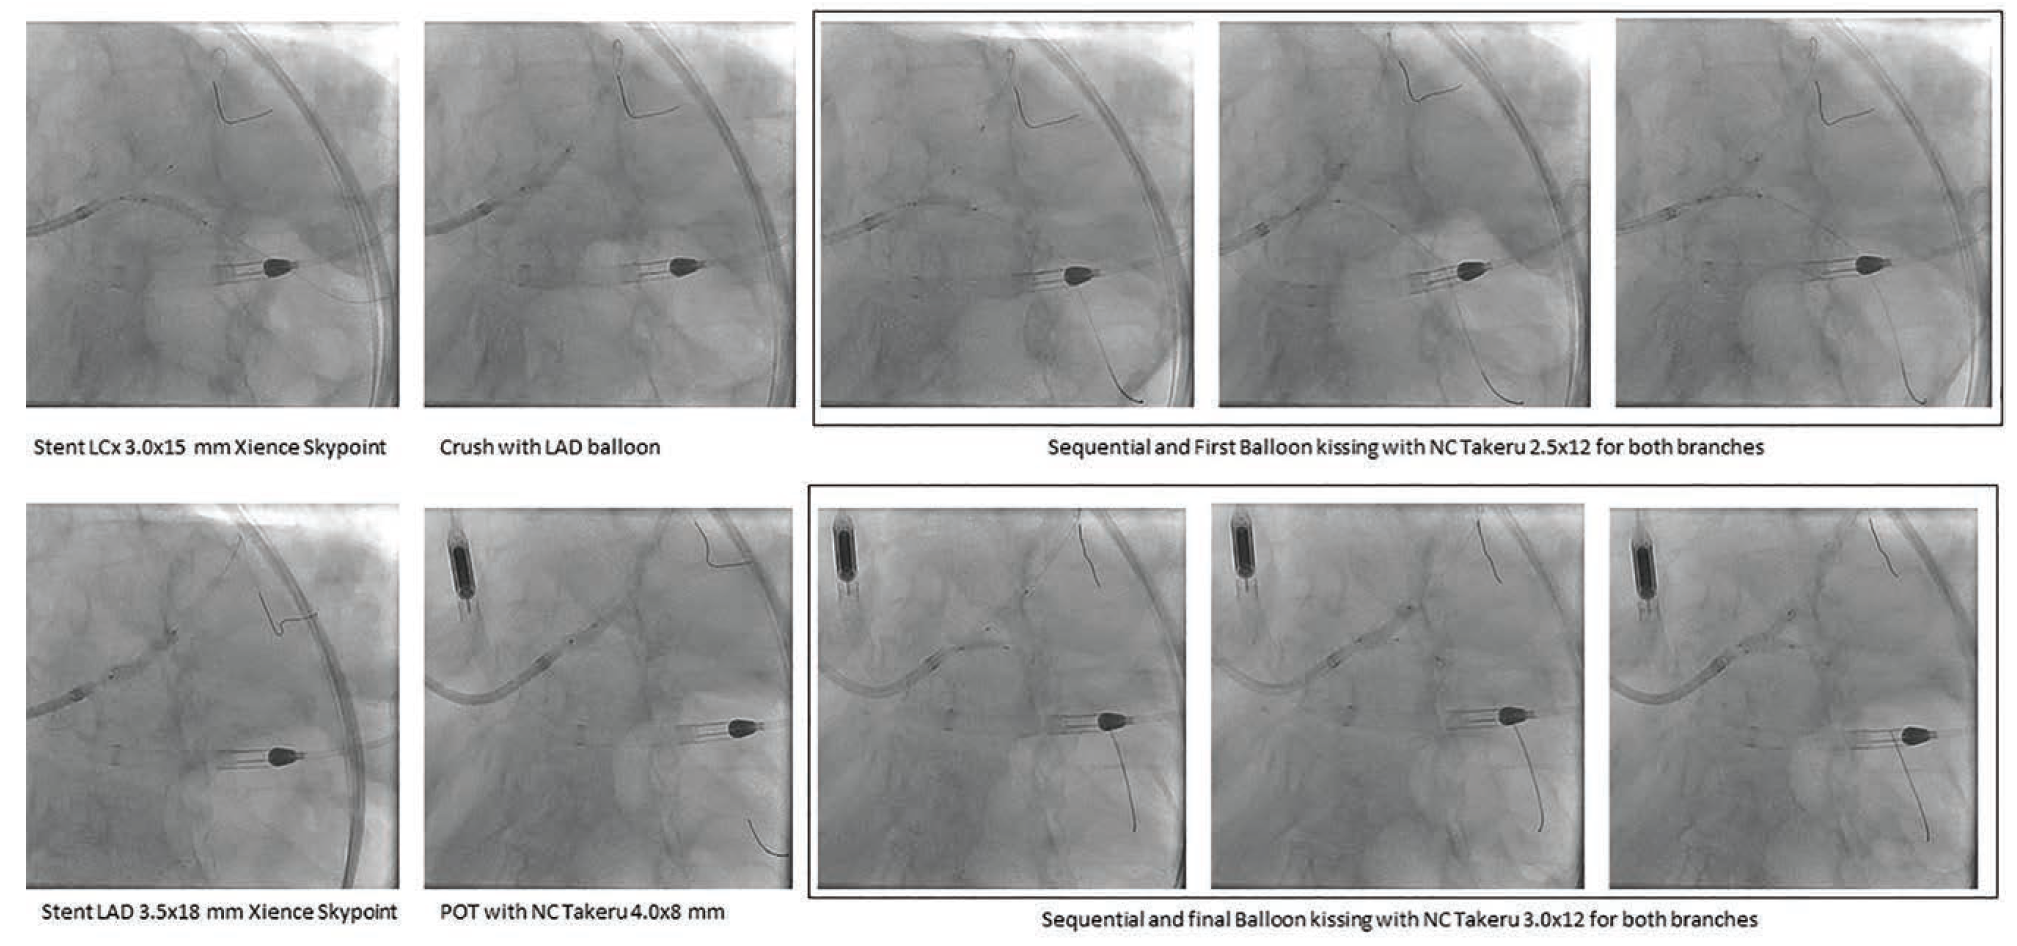

Based on the above assessment with IVUS, we elected to proceed with orbital atherectomy (Diamondback 360 orbital atherectomy system, Abbott Vascular) of the LAD, before which the LCX wire was removed and the LAD wire was swapped for a ViperWire with Flex Tip (Abbott Vascular) using a 1.7F distal tip FINECROSS® M3 Coronary Micro-Guide Catheter (Terumo Interventional Systems). Orbital atherectomy was performed with 4 passes at 80,000 RPM. The LAD (Figure 3) was treated with a 3.0 mm x 15 mm Takeru NC balloon. The LCX was rewired with the same Runthrough wire and a double kiss (DK) crush technique was used to stent the LM distal bifurcation with two Xience Skypoint drug-eluting stents (Abbott Vascular) (Figure 4 highlights the sizes and steps of the DK crush technique). IVUS assessment demonstrated well-opposed and well-expanded stents from the LAD and LCx into the distal LM (Figure 5).